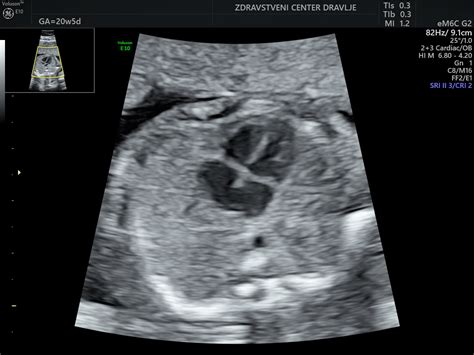

Med 20. in 22. tednom nosečnosti se običajno opravi ultrazvočna morfologija, ki je ključen pregled za oceno razvoja ploda. Ta pregled omogoča natančno določitev gestacijske starosti ploda s pomočjo meritev posameznih delov telesa, kot so prečni preseki in obseg glavice, obseg trebuha ter dolžina stegnenice.

Med pregledom se ocenijo različne strukture v glavi, vključno s talamusom, možganskimi polobli, malimi možgani in lobanjsko kotanjo. Pregledajo se tudi očnici, da se izključi hipotelorizem ali hipertelorizem. Ocenjuje se profil obraza, vključno z nosom, ustnicami in bradico.

Preveri se hrbtenica v različnih ravninah, trebušna prepona ter srce, ki se ocenjuje v štirih votlinah in pri izstopiščih velikih žil. Pregledajo se tudi ledvica in želodec, sečni mehur ter zgornji udov.

Posebna pozornost se posveti posteljici in popkovnici, kjer se ocenjuje debelina posteljice in struktura popkovnice z žilami. Merjenje dolžine materničnega vratu je pomembno za oceno tveganja za prezgodnji porod.

V tem tednu je ultrazvok še posebej zanimiv, saj omogoča vpogled v številne otrokove dejavnosti, vključno s požiranjem in sesanjem palca. Če ste se odločili za ultrazvok, je zdaj odličen čas, da zaprosite za ultrazvočne posnetke, saj je to morda vaš zadnji ultrazvok v nosečnosti, če poteka brez zapletov.